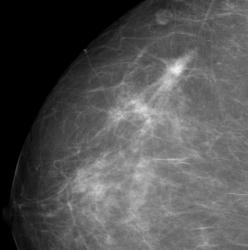

СЛУЧАЙ РЫБАКОВОЙ Л. А. "Инфильтрирующий рак правой молочной железы".

"Инфильтрирующий рак правой молочной железы".

Уважаемая Людмила Александровна, а как вы расцениваете участки, отмеченые желтыми стрелками? нет ли здесь мультицентричного рака?

Каюсь, вина моя. Людмила Александровна указала, что имеется "мультифокальный рост".